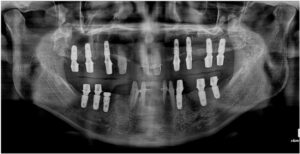

정밀한 검사를 위해

파노라마 사진을

촬영해 보았더니

치아를 단단하게 잡고 있어야 할 잇몸뼈가

녹아내려앉아있고,

염증이 있는 치아들도 다수 보였는데요.

양산전체임플란트를 진행하기에 앞서

파노라마 사진과 3D CT 촬영을 통해

잔존 치조골의 양과 두께,

상악동과의 거리, 하치조 신경의 위치,

눈에 보이지 않는 해부학적 구조물 등을

면밀하게 파악하는 과정을 통해

임플란트를 식립하기 좋은 위치와

식립 될 Fixture의 길이와

두께를 선정하였으며,